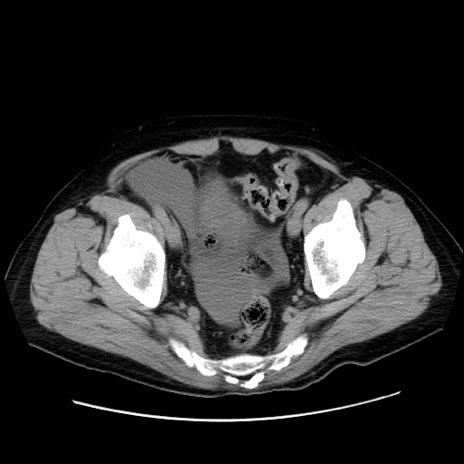

症例30(横断像)

【症例】80歳代男性

【主訴】臍周囲痛

【現病歴】約6時間前から臍下部痛が出現。次第に腹部膨隆・背部痛も生じてきたため来院。背部痛の場所は変化しない。

【身体所見】意識清明、BT 36.3℃、BP  131/87mmHg、P 87bpm、SpO2 100%(RA)、臍周囲自発痛・圧痛あり、反跳痛なし、自発痛部位に一致して板状硬あり、腹部膨隆、腸雑音減弱、CVA tenderness両側陰性。